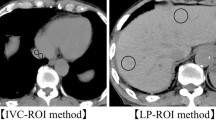

Quantitative image analysis

Mean CT numbers in Hounsfield units for the abdominal aorta at L2 and liver were measured in all patients with a CT console monitor by placement of a circular region-of-interest cursor, which ranged in diameter from 10 to 30 mm. CT numbers in the aorta were measured on unenhanced, HAP and PVP images. CT numbers in hepatic parenchyma were measured on unenhanced and PVP images. Focal hepatic lesions, blood vessels, bile ducts, calcifications and artefacts were carefully excluded from regions of interest. The degree of contrast enhancement is expressed as the change in CT number (∆HU), which was calculated by subtracting CT numbers on unenhanced images from those on contrast-enhanced images. We compared ∆HU for the abdominal aorta during HAP and for the abdominal aorta and liver during PVP between the two protocols.

The mean ∆HU for the abdominal aorta during HAP was significantly higher with the new tube protocol than with the conventional tube protocol (abdominal aorta, 322 ± 53 vs 290 ± 53, P < 0.01 [95 % confidence interval 8.5, 55.6]) (Fig. 4 and Table 4).

Results of the quantitative analysis. The mean ∆HU for the abdominal aorta during HAP was significantly higher with the new tube protocol than with the conventional tube protocol (abdominal aorta, 322 ± 53 vs 290 ± 53, P < 0.01). There was no significant difference in the mean ∆HU for the abdominal aorta and liver during PVP between the new and conventional tube protocols (abdominal aorta, 112 ± 18 vs 109 ± 14, P = 0.41; hepatic parenchyma, 55 ± 10 vs 54 ± 9, P = 0.87)

There was no significant difference in the mean ∆HU for the abdominal aorta and liver during PVP between the new and conventional tube protocols (abdominal aorta, 112 ± 18 vs 109 ± 14, P = 0.41 [95 % confidence interval −4.3, 10.4]; hepatic parenchyma, 55 ± 10 vs 54 ± 9, P = 0.87 [95 % confidence interval −3.9, 4.6]) (Fig. 4 and Table 4).